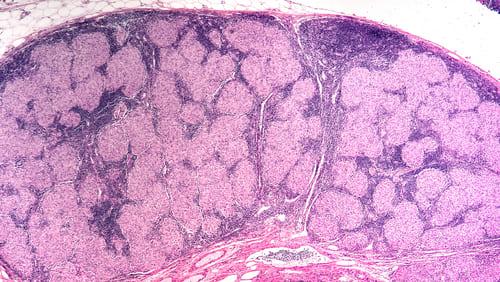

Sarcoidoza este o boală inflamatorie sistemică caracterizată prin formarea de granuloame non-caseoase – aglomerări de celule imune care pot apărea în diverse organe. În mod frecvent sunt afectate plămânii și ganglionii limfatici, dar pot fi implicate și pielea, ochii, inima sau ficatul, iar expresia clinică variază de la forme asimptomatice la manifestări care pot afecta semnificativ calitatea vieții. Această variabilitate în evoluție înseamnă că unii pacienți pot avea o boală autolimitantă, iar alții pot necesita monitorizare și intervenții pe termen lung.

Teste funcționale respiratorii, cum ar fi spirometria și măsurarea difuziunii, pot susține evaluarea gravității afectării pulmonare, iar proceduri invazive precum bronhoscopia cu lavaj bronhoalveolar și diverse tehnici de biopsie (transbronșică, transbronșică ghidată sau chirurgicală) pot ajuta la obținerea materialului pentru examen histologic când este necesar. Rezultatele histologice și clinice sunt interpretate împreună de echipă pentru a evita concluzii izolate.

Echipa multidisciplinară poate completa evaluarea cu investigații pentru implicarea altor organe, cum ar fi teste sanguine uzuale, markerii inflamatorii, inclusiv nivelul ACE și calcemia, ECG și imagistică cardiacă pentru suspiciunea de afectare cardiacă, precum și examen oftalmologic; aceste teste pot contribui la documentarea extinderii bolii, dar nu sunt definitive individual. Deciziile diagnostice și terapeutice se stabilesc proactiv în colaborare cu specialiștii, adaptate la contextul fiecărui pacient.